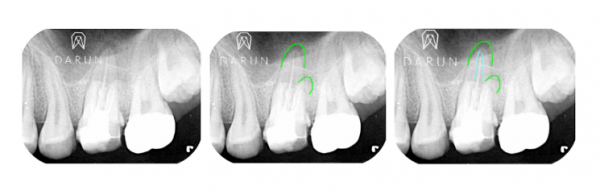

크라운 위한 준비 후 한 컷.

표시된 것처럼 심상치 않은 느낌이에요.

파라색으로 표시한 부분처럼.

치아뿌리 안쪽 관에 비어있는게 많은 것 처럼 보여요.

오염물질! 보철물에서 sealing이 중요하다고 했었죠.

신경치료도 마찬가지입니다.

Sealing이 중요해요.

어떻게 든 Bacteria 침입을 막기 위한거죠.